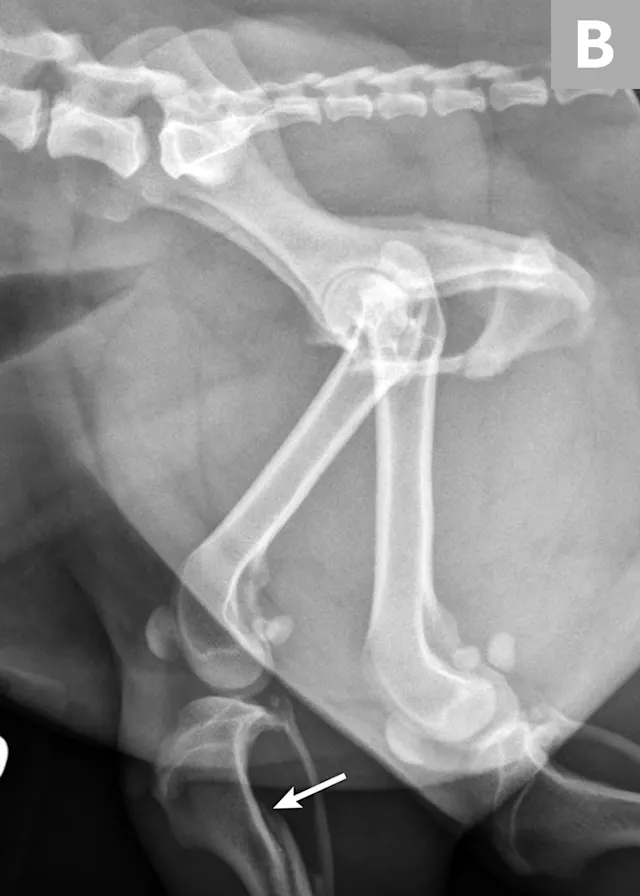

There are many different types of pelvic fracture configurations, and nearly half of pelvic injuries in dogs and cats involve fractures of the ilium.3,4,7,8 Clinically significant fractures involve the weight-bearing axis of the pelvis that includes the ilium and acetabulum (Figures 1-3). Although not a fracture, sacroiliac luxation is potentially significant because the sacroiliac joint is a component of the weight-bearing axis of the pelvis. Unilateral or bilateral fractures or luxations may occur, and it is common for patients to have a combination of pelvic injuries.3,4,7,13

FIGURE 1A

An 11-year-old intact female Welsh corgi with injuries of the weight-bearing axis of the pelvis. Ventrodorsal (A) and lateral (B) projection images show a left sacroiliac luxation with cranial and ventral displacement (black arrow). Pubic fracture with lateral displacement (dashed arrow) and an oblique tibial fracture (white arrows) were additional comorbidities. The tibial fracture was treated surgically with an internal plate fixation, and the pelvic injuries were managed conservatively.